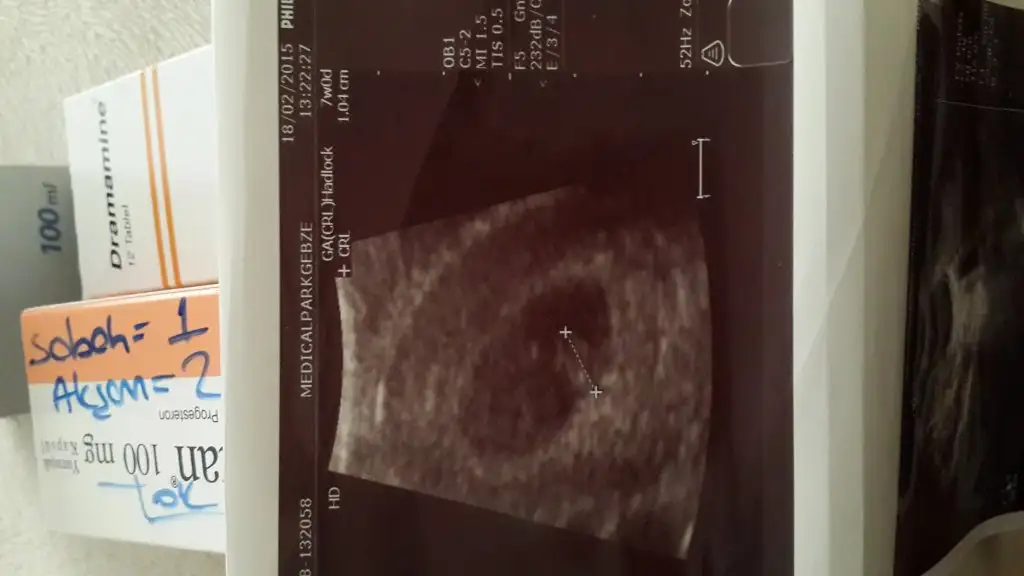

Mide bulantım için Dramamine verdi birde rennie şurup

Sat a göre 6+4 ultrasona göre 7 haftalık çıktık.

Bebişin ilk ultrason görünyüsünü paylaşıyorum Rabbim nazarlardan korusun

Son olarak Gebze'de Medicalpark Hastanesi Opr. Dr. Amanullah Çağatay'a gidiyorum